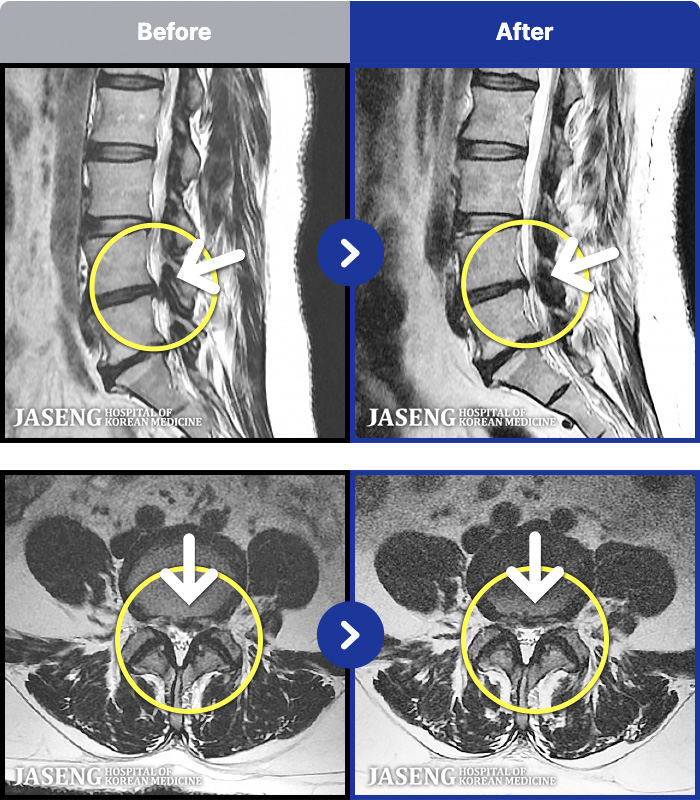

- MRI ġ

MRI ġ

53 MRI ũ ʸ Ȯϼ.